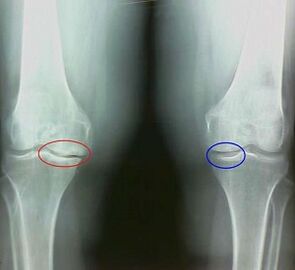

Adibidez, zein da belauneko artikulazioaren artritisaren eta artrosiaren arteko aldea? Artritisarekin, ehun artikuluen maskor sinovial gertatzen da. Horrek tenperaturaren gehikuntza eragiten du artikulazioan.

Elkarguneak, mina sindrome iraunkorra garatzen da, mugimenduan zehar areagotuz. Artrosez, mina jarduera fisikoa egin ondoren gertatzen da, artikulazioan egindako krisi edo klik bat entzun ahal izango duzu, pixkanaka juntura deformatu eta mugikortasuna galtzen du.

Kartilagoaren eta hezur-ehunaren porrota ahaztutako egoeran dagoen etapetan gertatzen da. Artrosia, kartilagoaren ehuna lehenik eta behin, hezurrak, mintz sinovialaren hantura bigarren mailako jatorria da, hau da, haien aurrekariak garatzen ditu.

Sintomak eta diagnostiko diferentzialen xehetasunak patologia zehaztasunez zehaztuko du - artritisa edo artrosia.